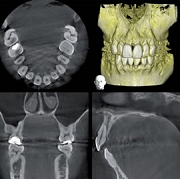

当院では、最新の歯科用CTを導入しました。

従来のレントゲン画像は平面像(二次元)でしたが、歯科用CT画像は立体画像(三次元)でみることが出来ます。

ですから、インプラントや歯周病などの診断に有効で、従来の平面画像では難しいとされた骨の幅の確認などが行えます。CT撮影で様々な角度から診断することで、正確な診査・診断に役立ち、より安全で確かな治療を行うことが可能となりました。

CT画像からは、骨の形や欠損状態がわかるだけでなく、神経の位置や向きなどもしっかり把握できますので、特に、以下のような治療で役立っています。